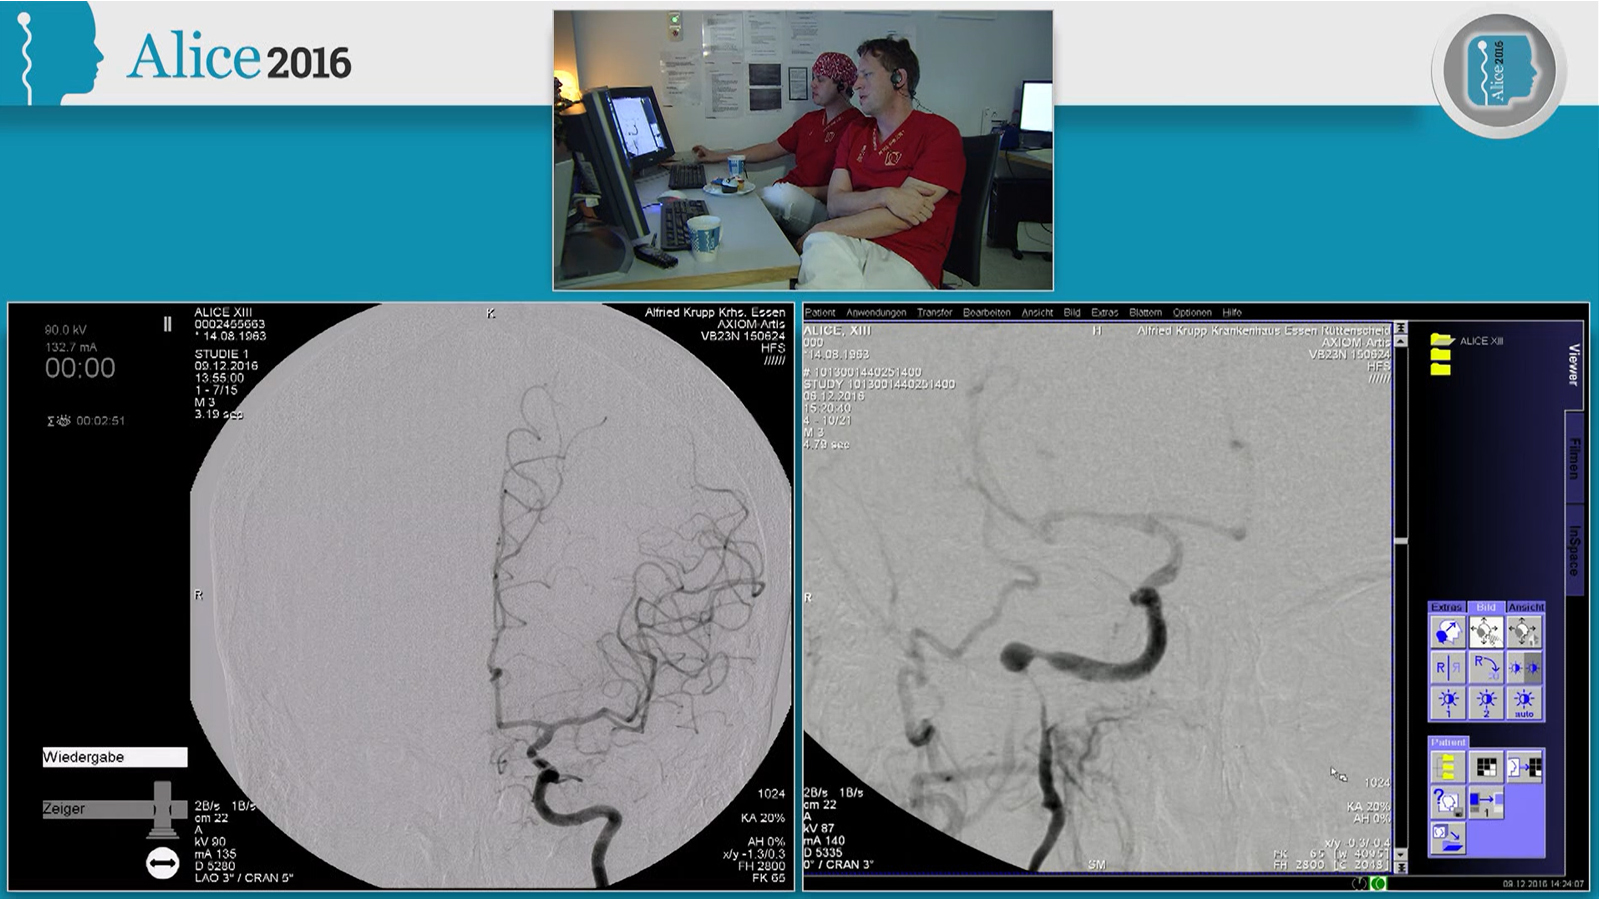

Acute ruptured dural fistula of the superior petrous sinus treated by transvenous embolization

Dural fistula of the marginal sinus treated by dual micro catheter venous approach and occlusion with coils and onyx

Dural fistula of the tentorium treated by transarterial pressure cooker embolization

Dural fistula treated by transarterial pressure cooker embolization

Extensive fast progressive Dural fistula treated by transvenous embolization with PHIL under double balloon protection of the sinus

Dural fistula of the condylar confluence treated by transvenous embolization with balloon protection of the sinus